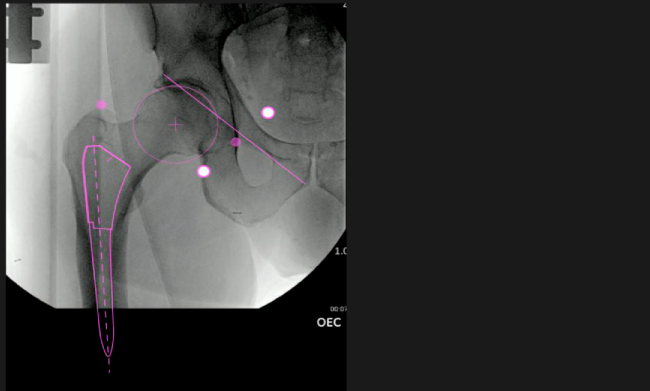

Desplazamiento y offset para posicionamiento óptimo del componente (vástago) femoral.

Verificación de la posición deseada del implante que potencialmente puede ayudar a reducir la probabilidad de dislocación protésica y aumentar la estabilidad de la articulación.

Anotaciones digitales y herramientas de análisis de longitud de pierna.